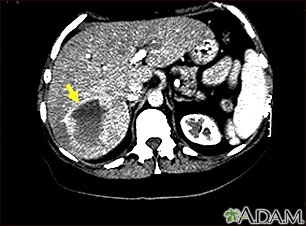

A hepatic hemangioma is a liver mass made of widened (dilated) blood vessels. It is not cancerous.

- CT scan of the liver